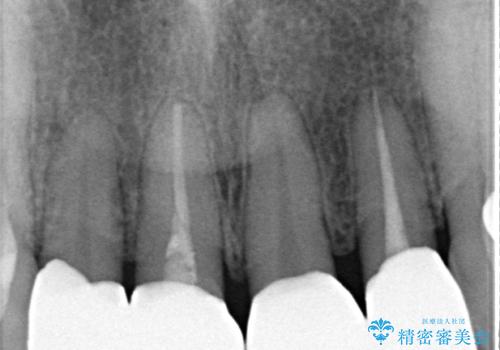

- 他院で治療したラミネートベニアをきれいにやり替えたいと来院された患者様です。

ラミネートベニアの欠けてしまっているところをコンポジットレジンで修復してあり、変色が目立ちます。

根管治療をしている歯もあるため、オールセラミッククラウンにすることとしました。

再根管治療は希望されなかったため、土台のやり替えから行いました。